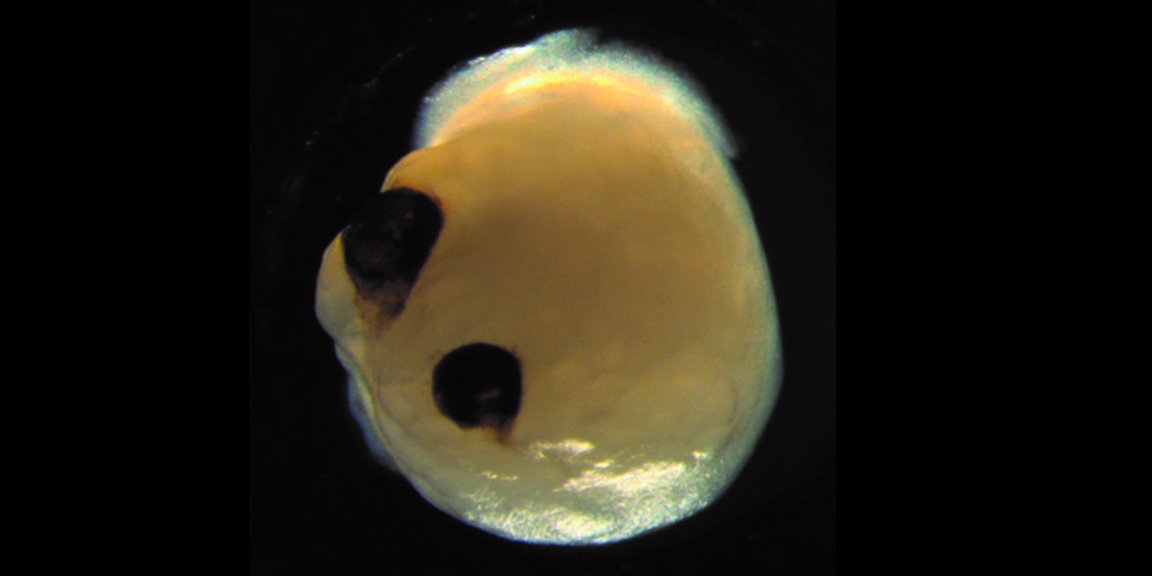

The majority of the brains contained “optic cups,” structures where the retinas later develop in the mini brains’ much larger and in vivo counterparts.

During an experiment, the researchers were able to generate optic cups in 72 percent of 314 brain organoids.

These eye precursors contained several kinds of retinal cell types that were able to form active neuronal networks that responded to light, according to the statement.